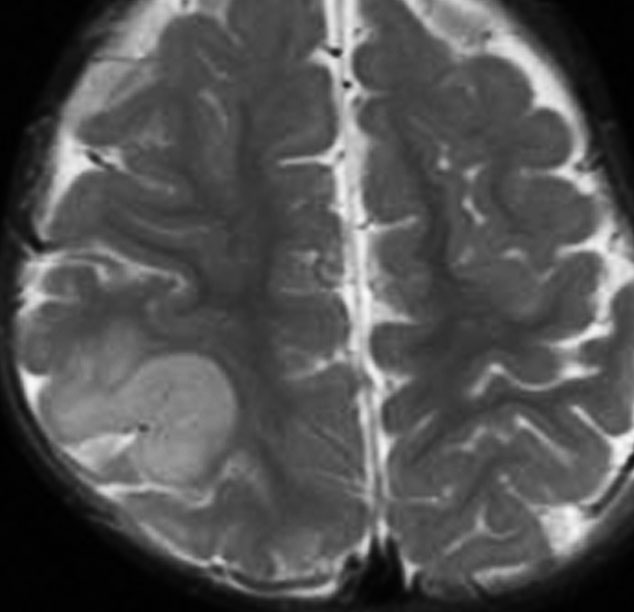

2歳時に偶然発見された,大脳皮質の限局性異形成です。10歳まで症状はでていません。

右側頭葉中側頭回の皮質が厚くなっています。T1強調画像では等信号で見づらいですが,下のフレア画像とT2強調画像では高信号になるのでわかります。

低悪性度グリオーマと間違われることがありますが,大脳皮質だけが異常な信号になっていて,皮質下白質に異常所見がないことが鑑別点です。